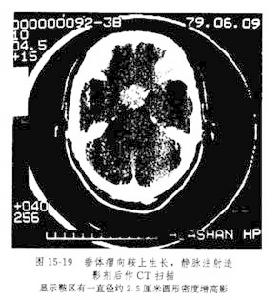

2.頭顱CT 正常垂體在冠狀面上呈橢圓形,高度為2~8.4mm寬度為7~21mm按上緣形態分為3型:平坦型凹陷型和隆起型前兩者多見,而隆起型常見於妊娠、月經期的青春期女性平掃垂體密度均勻一致和腦組織相等或稍高,增強後可均勻增高。

(1)垂體大腺瘤:大多數垂體腺瘤與周圍正常垂體組織對比是低密度影極少數呈高密度影垂體上緣成凸形增強後腫瘤明顯增高,腫瘤中有壞死和囊性變在增強後更清楚。腫瘤較大時冠狀位可顯示其向上侵入鞍上池,壓迫或侵襲視交叉自下壓迫鞍底或破入蝶竇,向一或兩側侵及海綿竇。急性垂體卒中,CT可見瘤內高密度影。

(2)垂體微腺瘤:頭顱CT有時診斷困難,主要是依靠臨床表現和激素測定。增強的CT徵象可能有幫助:增強的垂體腺中有局限性低密度區,有時也可見小環狀增強結節影;其他徵象還有垂體上緣隆凸局部或偏側隆凸更有意義;垂體高度增加常>8mm;垂體柄偏移鞍底局部骨質變薄破壞或鞍底傾斜等在冠狀面圖像上,腫瘤底部緊貼鞍底或鞍底骨質異常,多為垂體腺瘤。